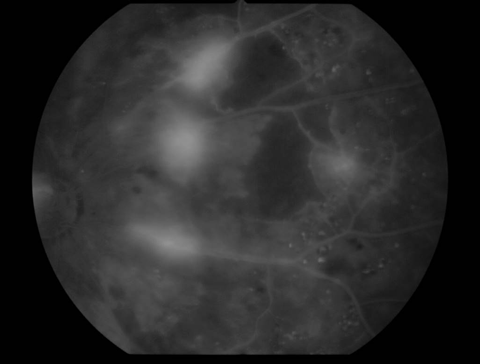

2.前増殖糖尿病網膜症

| 中期の網膜症 | 毛細血管がつまり血管閉塞を生じます。血管閉塞した網膜は虚血におちいり、軟性白斑という所見が生じます。 | 虚血網膜は放置することによって、新生血管が生じ、硝子体出血や増殖膜のもとになるため、この段階で、的確なレーザー治療(網膜光凝固術)をしっかりと行っておくことが非常に重要になります。 |

軟性白斑 |